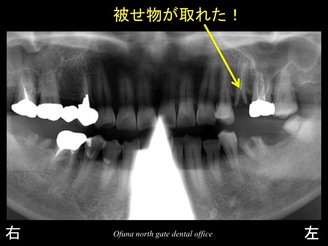

それでは初診時のレントゲンから見てみましょう。

右下の奥歯と左下の奥歯の被せ物が取れてしまったため、

『奥歯で物が噛めない!』との問題から当医院を受診されました。

診査をすると被せ物が取れた歯は、虫歯が非常に深い状態でした。

上顎の左側の奥歯も被せ物が取れている状態でした。

これらの歯は神経がない歯です。

以下の青丸:●が神経がない歯です。